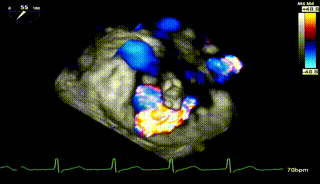

3D

怎么上穿刺鞘攻克巨大左房伴转位穿刺难关!温医大附一院周浩教授团队创新应用“导丝定位+可调弯鞘”技术完成高难度TEER手术_https://www.jmylbn.com_新闻资讯_第9张

3D带彩

怎么上穿刺鞘攻克巨大左房伴转位穿刺难关!温医大附一院周浩教授团队创新应用“导丝定位+可调弯鞘”技术完成高难度TEER手术_https://www.jmylbn.com_新闻资讯_第10张

1.二尖瓣重度关闭不全(4+),瓣环明显扩大(AP径4.6cm,LM径3.9cm),扁平,关闭时瓣叶对合不佳(carpentier I),1-3区均可见反流束,返流宽度达26mm;肺静脉频谱呈收缩期反向。

2.画迹法测得二尖瓣瓣口面积约8.8cm²。

3.PISA法测得EROA=0.57cm²,Rvol=77ml,r=11mm。

4.二尖瓣前叶(A2)长度29mm,后叶(P2)长度11mm。

5.左房巨大(三径86*84*114mm),右房巨大(内径114*86mm),CFI提示极重度三尖瓣反流,Teich法测得EF为70.1%。